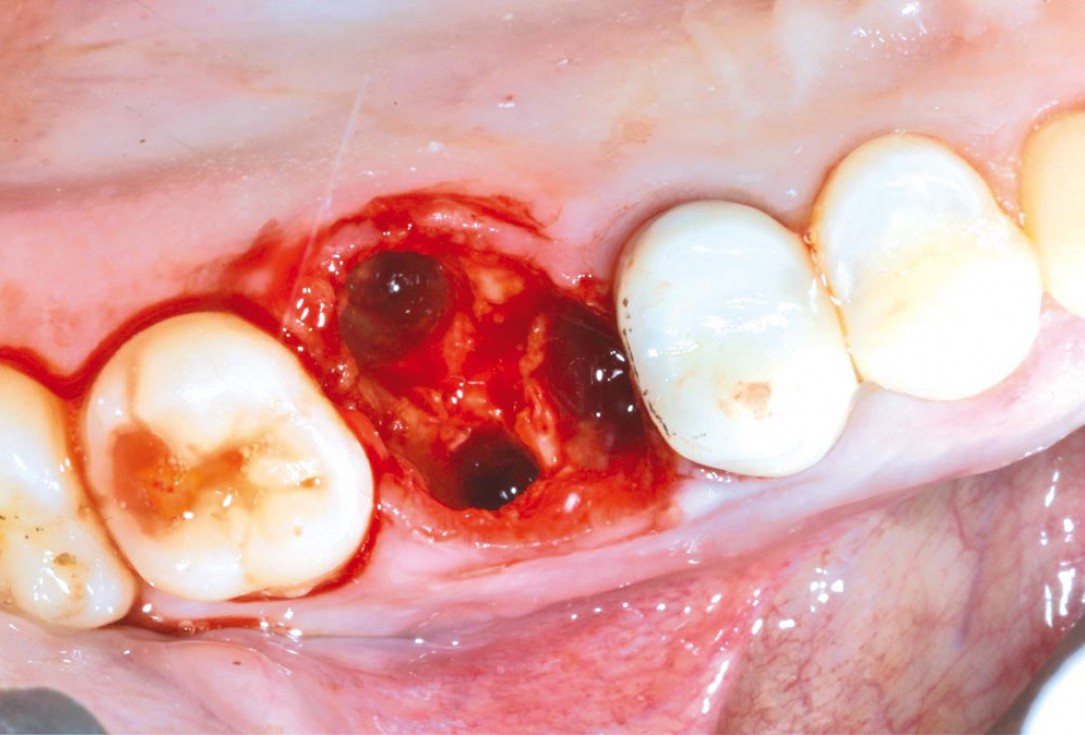

2/11 - Atraumatic tooth extraction with intact bony wallsSealing of a postextraction socket with mucoderm® - Dr. M. Frosecchi

Intact socket following atraumatic tooth extraction